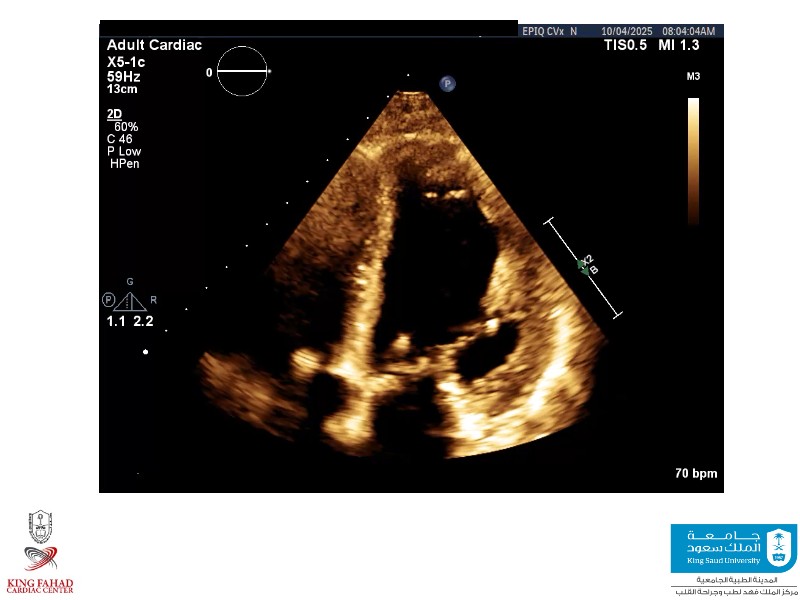

This session helps you anticipate and address complex scenarios such as mitral valve-in-valve, TAV-in-SAV, and valve-in-valve-in-valve procedures. Learn from expert case discussions that explore procedural strategies, technical challenges, and best practices to optimize outcomes in redo structural heart interventions.

- To anticipate and manage second valve scenarios with SAPIEN 3 Ultra RESILIA, including mitral valve-in-valve, TAV-in-SAV, and TAV-in-TAV

- To understand procedural strategies and challenges in complex redo scenarios using SAPIEN 3 Ultra RESILIA